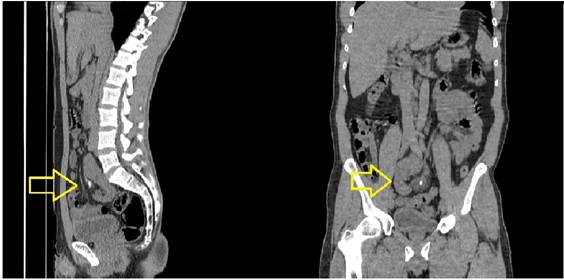

Fig. 1 El riñón derecho se encuentra hacia la pelvis con presencia de múltiples cálculos.

A la exploración con signos dudosos de irritación peritoneal. Por lo que se indica manejo sintomático y realización de Urotac. Éste revelo que el riñón derecho se encontraba hacia la pelvis con presencia de múltiples cálculos (Fig. 1), el riñón izquierdo era de localización normal, por lo que se interconsulta al servicio de Urología (Fig. 2).